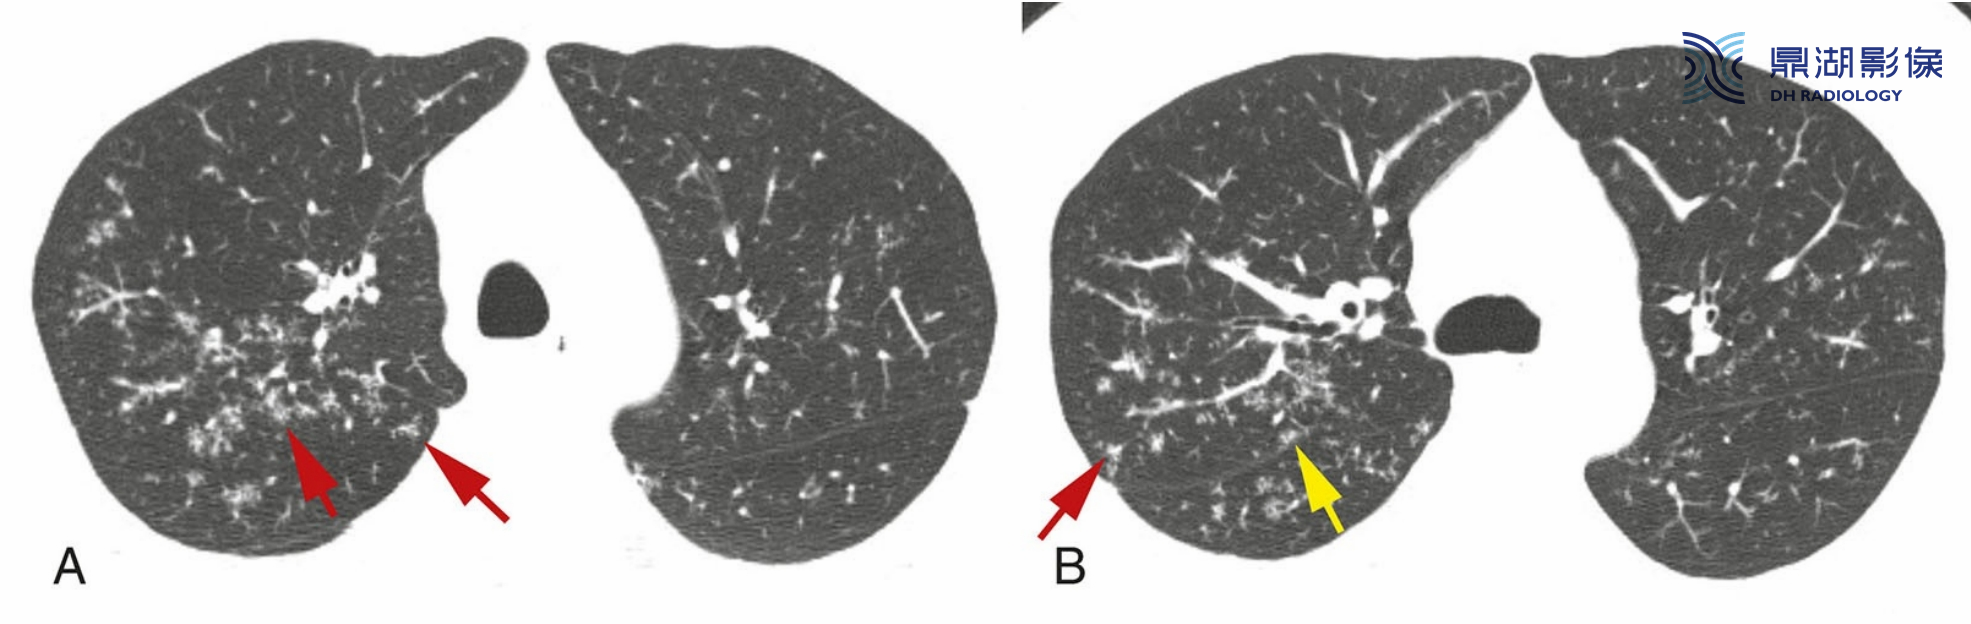

4c3490966e64a4453dcb6053827bc11b.png

结节病伴小叶中心性结节。结节主要分布于小叶中心且边界模糊(红箭)。胸膜下可见数个散在结节(黄箭,B)。支气管血管周围间质延伸至肺外周,与小叶中心支气管和动脉相连。在一些患者中,结节病肉芽肿主要累及上述结构,形成边界清楚或模糊的小叶中心性结节。

上述这种表现为小叶中心性结节的结节病,与结核较难鉴别。